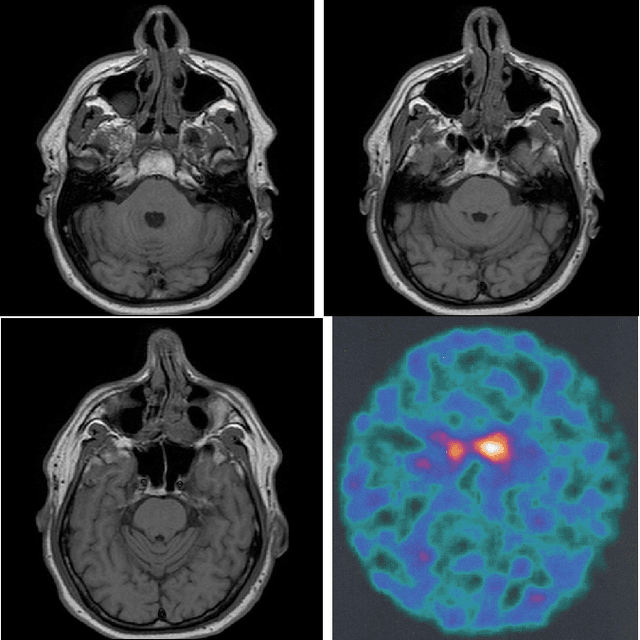

Abstract:This paper presents a new method for medical diagnosis of neurodegenerative diseases, such as Parkinson's, by extracting and using latent information from trained Deep convolutional, or convolutional-recurrent Neural Networks (DNNs). In particular, our approach adopts a combination of transfer learning, k-means clustering and k-Nearest Neighbour classification of deep neural network learned representations to provide enriched prediction of the disease based on MRI and/or DaT Scan data. A new loss function is introduced and used in the training of the DNNs, so as to perform adaptation of the generated learned representations between data from different medical environments. Results are presented using a recently published database of Parkinson's related information, which was generated and evaluated in a hospital environment.